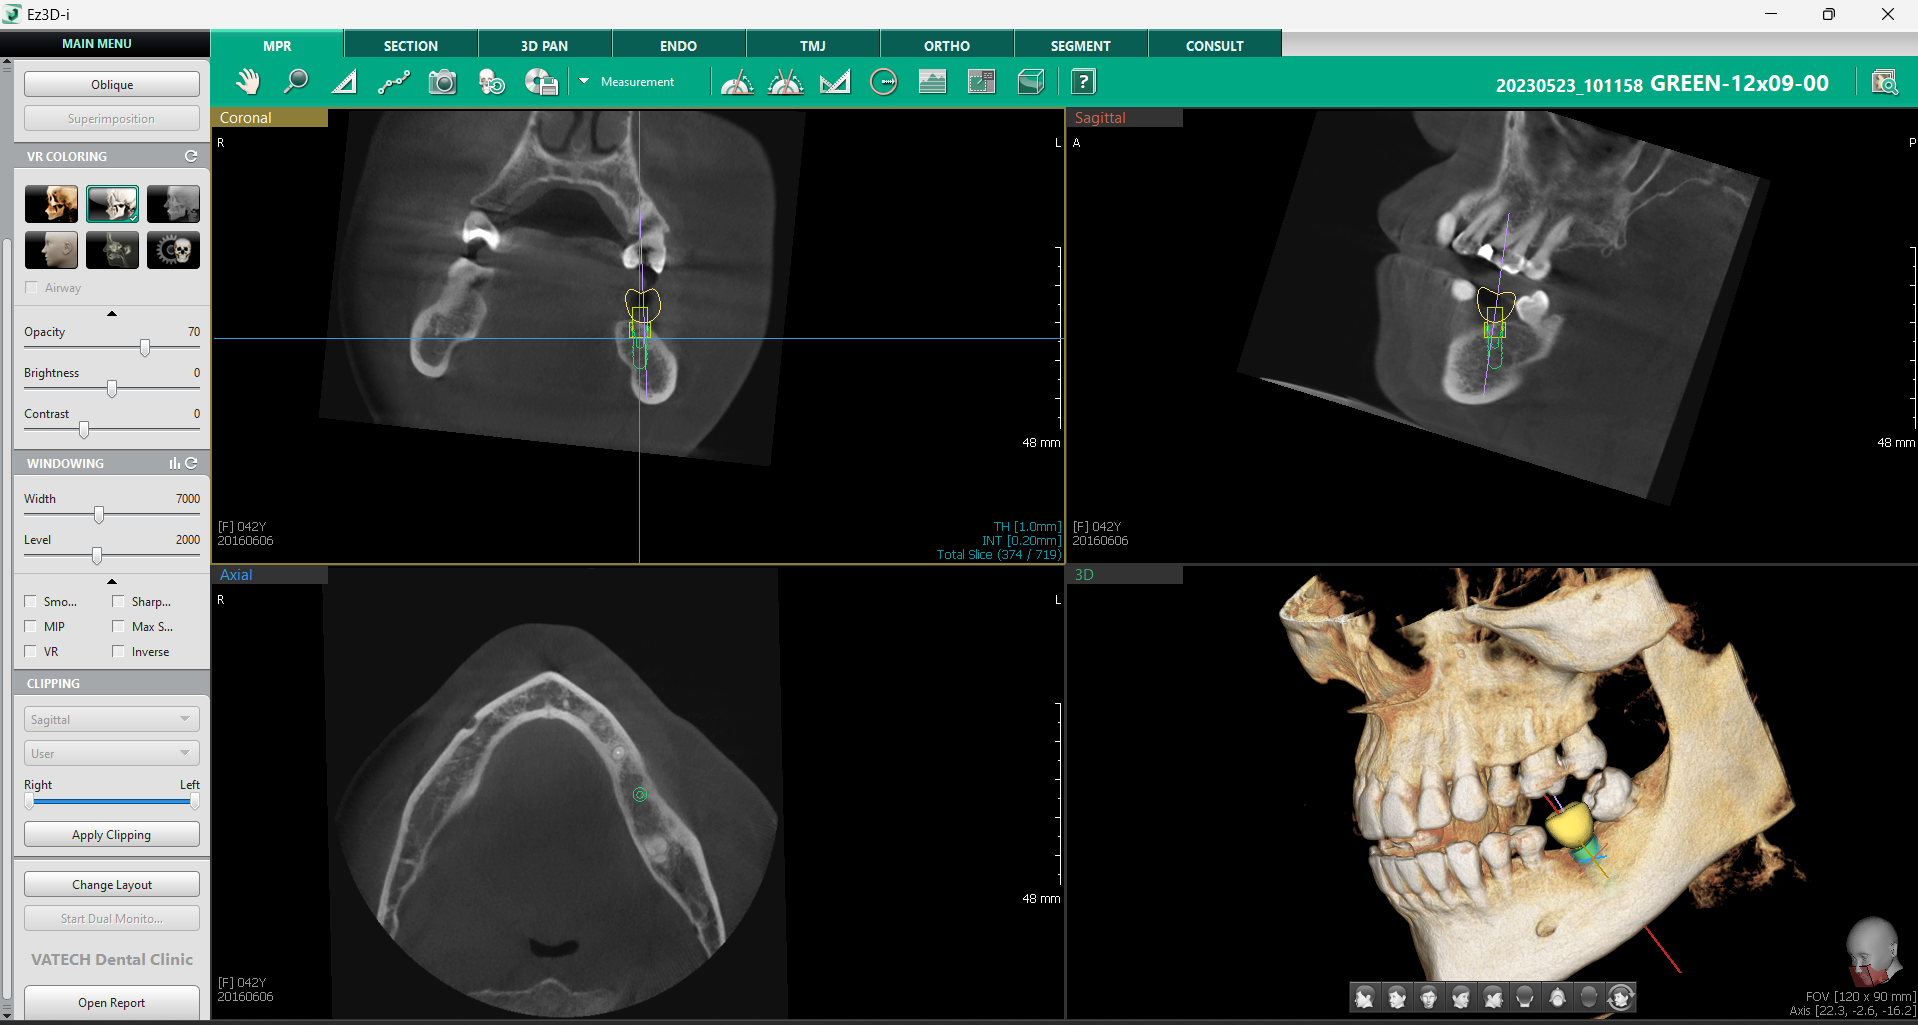

a. Setarea axei MPR

Funcția Set MPR Axis este un instrument esențial pentru verificarea poziționării corecte a implantului, oferind o metodă rapidă și eficientă de analiză a sănătății osoase și a plasării implantului în raport cu structurile adiacente.

Printr-un simplu click dreapta pe implant și selectarea opțiunii „Set MPR Axis” din fila MPR, software-ul realiniază automat toate planurile imagistice conform poziției implantului. Această funcție oferă medicului o perspectivă detaliată asupra implantului în raport cu densitatea osoasă și permite ajustarea rapidă a poziției înainte de finalizarea procedurii.